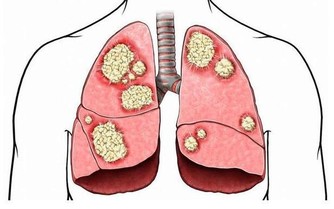

一位正值人生顛峰時刻的大學教授,卻被診斷出罹患了早發性的阿茲海默症。

目前還沒有任何藥物可以治癒失智症,

但卻可以靠後天的努力,來延緩完全發作與退化的時­機。

患者應養成終身學習的習慣,搭配規律地運動及健康飲食,

在家人的陪伴下積極再次走­入人群,也許一切都像未曾發生過。